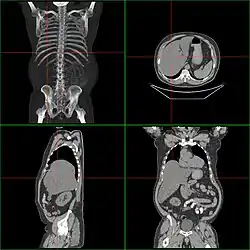

Гепатомегали́я — патологическое увеличение размеров печени.

Если размер печени по l. medioclavicularis dextra превышает 12 см или пальпируется левая доля в эпигастральной области, говорят об увеличении печени. Важно исключить опущение печени (например, при хронической обструктивной болезни лёгких или вздутии правого лёгкого) или расположение в правом верхнем квадранте других тканей (увеличенный желчный пузырь, опухоль почки или кишки). Размеры печени лучше определить посредством КТ или УЗИ. Важно оценить контуры и рисунок ткани органа; Увеличение тех или иных участков ткани; «каменистая» консистенция предполагает наличие опухоли; боль при пальпации говорит о воспалении (гепатит) или быстром увеличении размеров органа (недостаточность правого сердца, синдром Бадда — Киари, жировая инфильтрация).